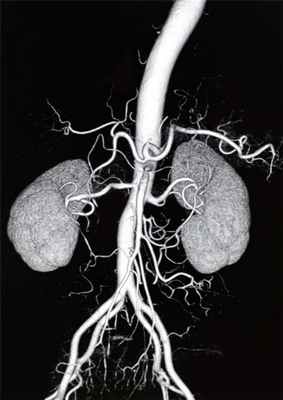

4. Ангиография (аортография) – является инвазивным методом исследования, позволяющим при помощи контраста визуализировать аорту и ее ветви. Этот метод обладает высокой диагностической ценностью, однако недостатком его является инвазивность (прокол сосуда), рентгеновское излучение, а также введение контраста, который может быть противопоказан при хронической почечной недостаточности;

5. МРТ, КТ аорты – является «золотым стандартом» диагностики аневризмы аорты и ее осложнений. Является дорогостоящим методом исследования и проводится в специализированных центрах.

Аорта разделена диафрагмой на грудную и брюшную аорту. Если АА образовалась в брюшном отделе, что чаще и происходит, то речь идет об аневризме брюшной аорты (АБА).

2. Современный метод лечения - эндоваскулярная имплантация стент – графта (внутрисосудистого протеза).

Этот вид операции позволяет через два небольших разреза на бедре, под видеоконтролем, проникнуть по сосудам в аорту и заменить ее поврежденный участок изнутри. Сосудистый протез, уложенный в специальную систему, доставляется до места АА, расправляется прямо в полости аневризмы. Всю процедуру осуществляет врач-эндоваскулярный хирург под контролем рентген-установки. Таким образом, протез берет на себя силу воздействия системного артериального кровотока на слабые растянутые стенки аорты.